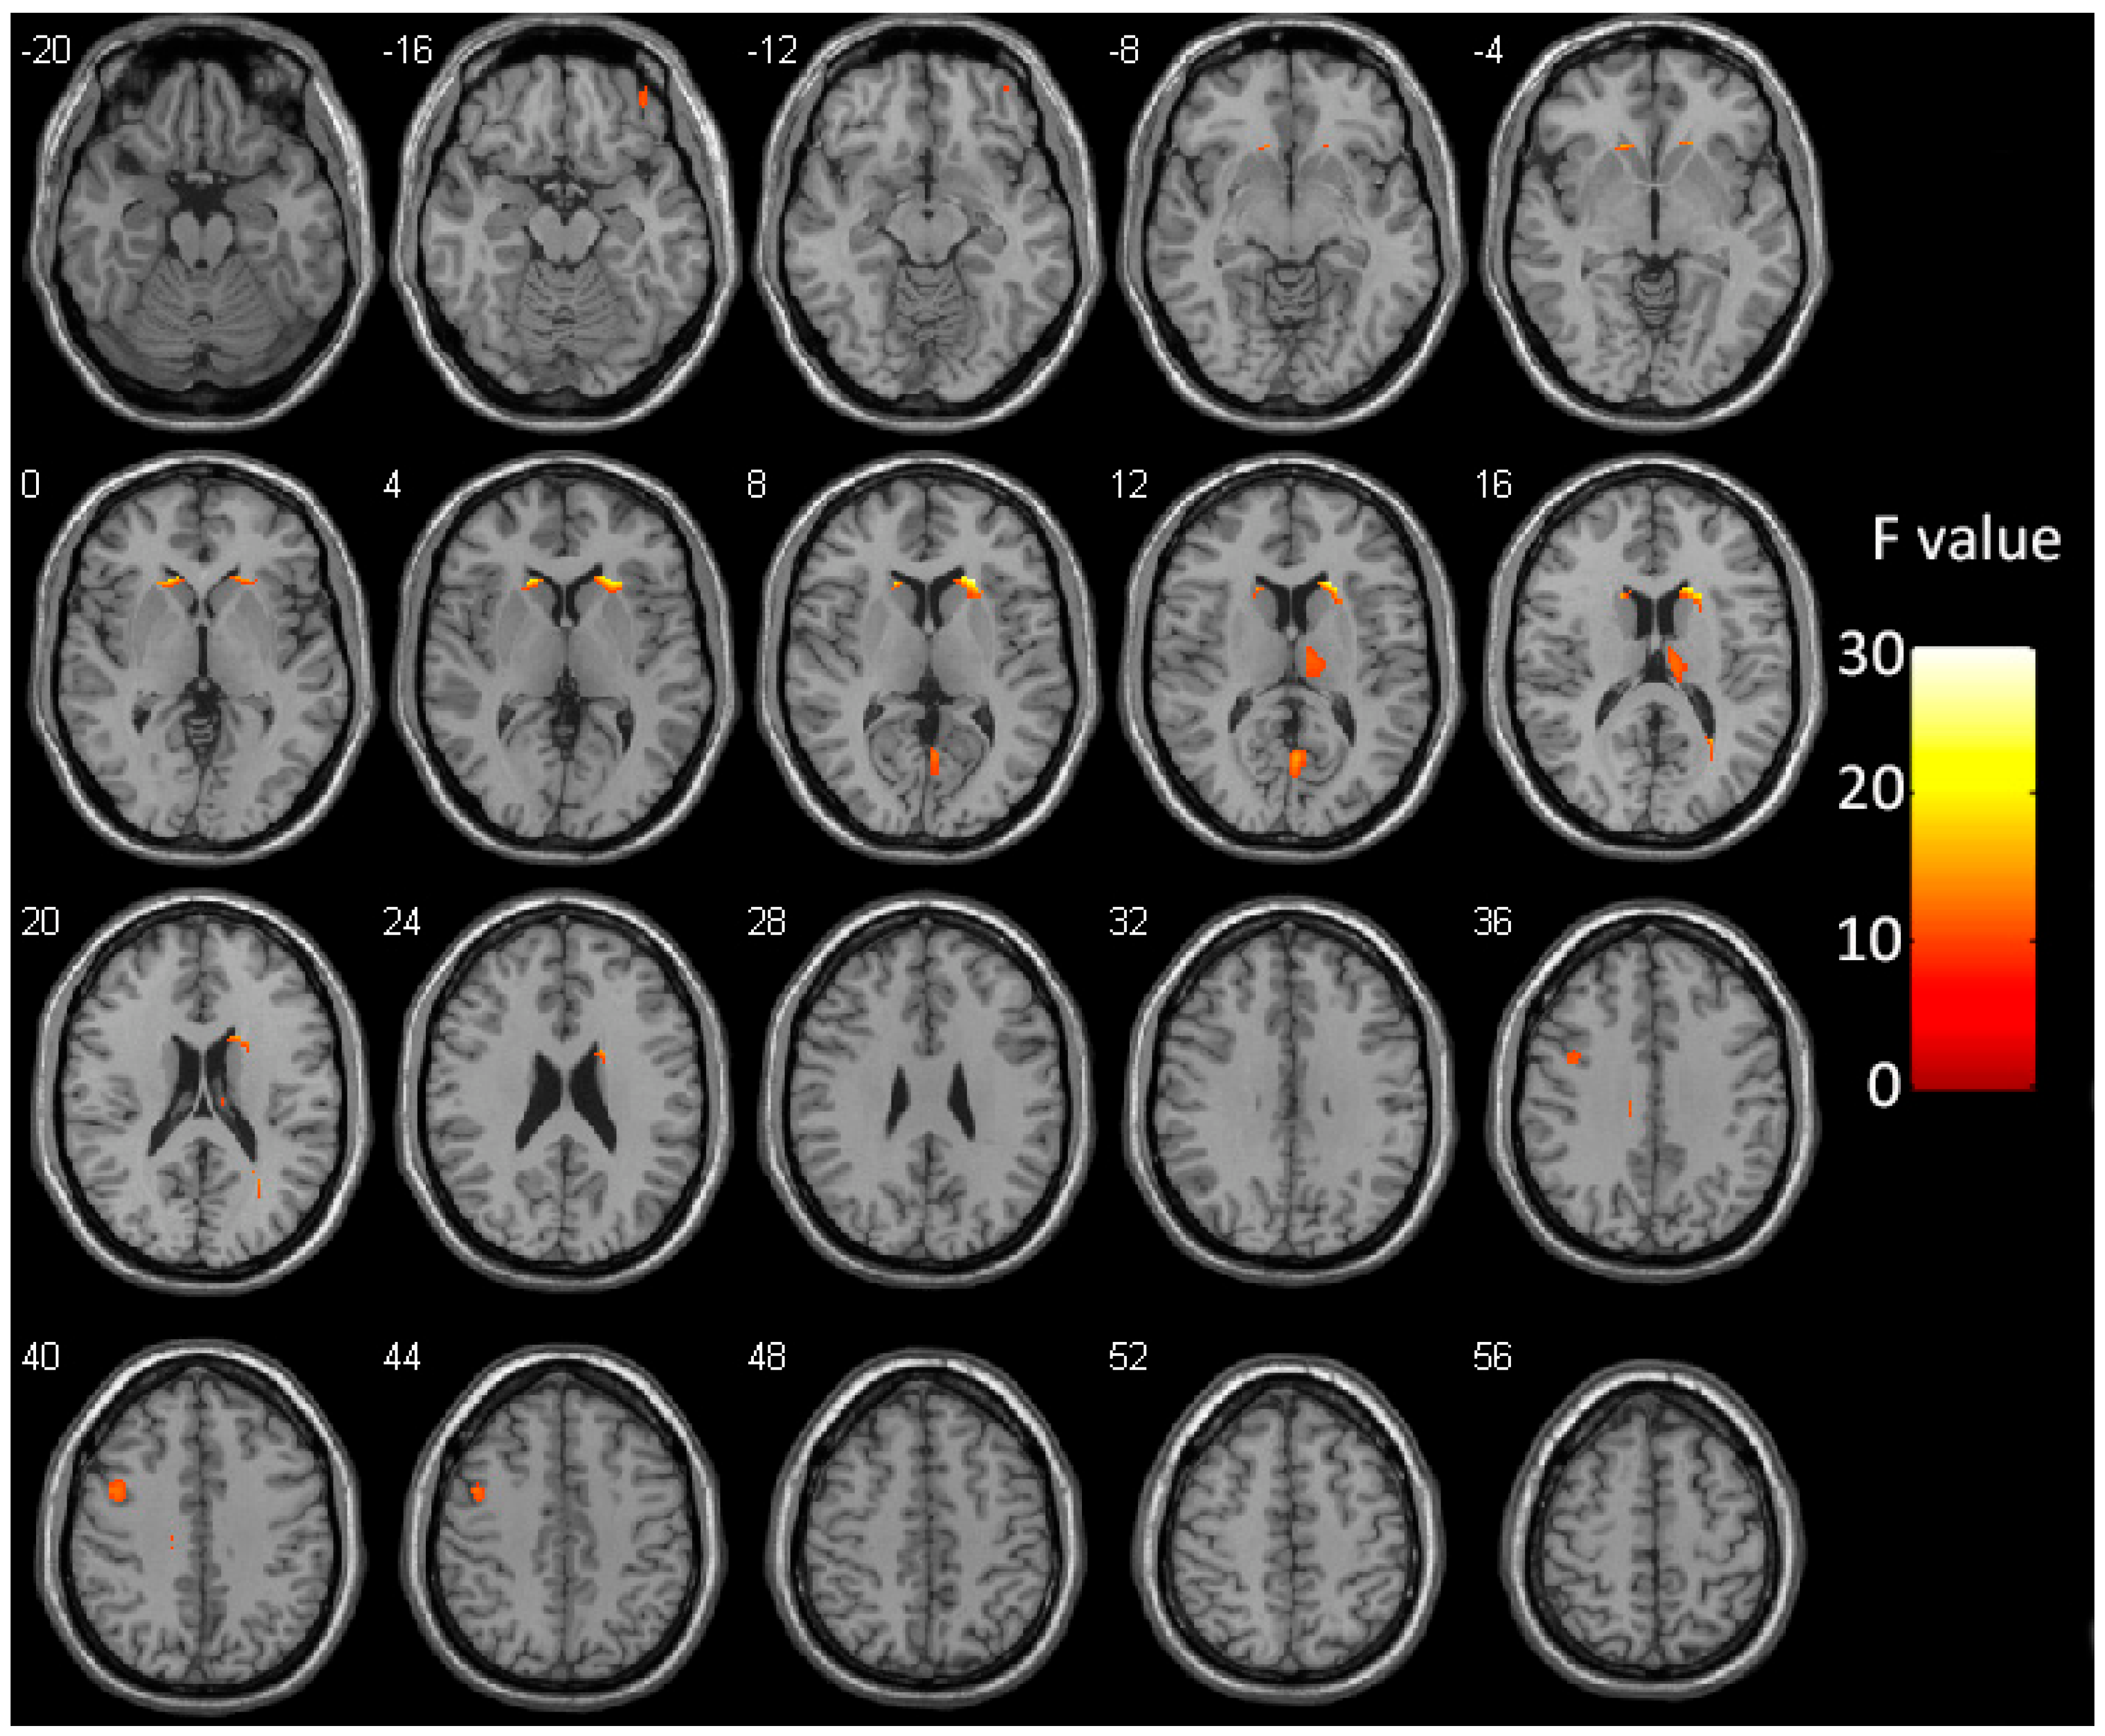

| Brain Region | Hemisphere | Cluster Size | MNI Coordinates | Peak F Values | ||

|---|---|---|---|---|---|---|

| X | Y | Z | ||||

| Caudate | R | 387 | 21 | 22.5 | 10.5 | 28.14 |

| Thalamus | R | 282 | 9 | −16.5 | 15 | 12.24 |

| Calcarine cortex | Bilateral | 198 | 1.5 | −64.5 | 10.5 | 15.34 |

| Precentral gyrus | L | 177 | −46.5 | 4.5 | 42 | 12.84 |

| Caudate | L | 148 | −18 | 24 | 4.5 | 21.13 |

| Orbitofrontal cortex | R | 61 | 37.5 | 45 | −18 | 11.16 |

| Cingulate gyrus | L | 58 | −12 | −24 | 33 | 12.57 |

| Sub-gyral of the temporal lobe | R | 45 | 27 | −55.5 | 18 | 16.86 |